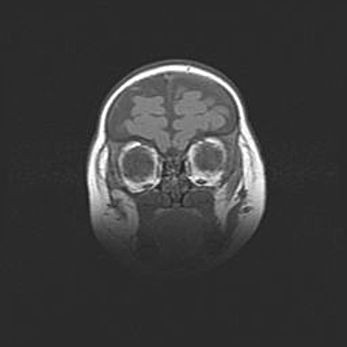

Аномалия Денди-Уокера. Признаки гипоплазии мозолистого тела.

Возраст: 5 месяцев 3 дня

Вес: 5550 г

Пол: мужской

Окружность головы: 39 см

Срок гестации: 40 недель

Аномалия Денди-Уокера – это порок развития головного мозга, для которого характерна триада симптомов: гипотрофия или аплазия червя мозжечка и/или полушарий мозжечка, расширение четвёртого желудочка с формированием ликворной кисты задней черепной ямки, гипертензионная гидроцефалия различной степени.

Гипоплазия мозолистого тела относится к дефектам внутриутробного этапа развития мозговой ткани, возникающим в процессе закладки структур головного мозга, что происходит на начальных этапах развития эмбриона.